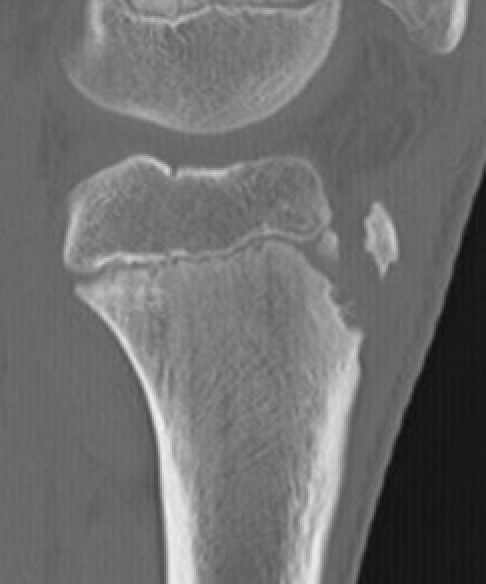

CT / MRI scan

CT scan - ensure fracture doesn't involve the physis / disrupt articular surface

Type IB

Type IIB

Type III

Comminuted Type III